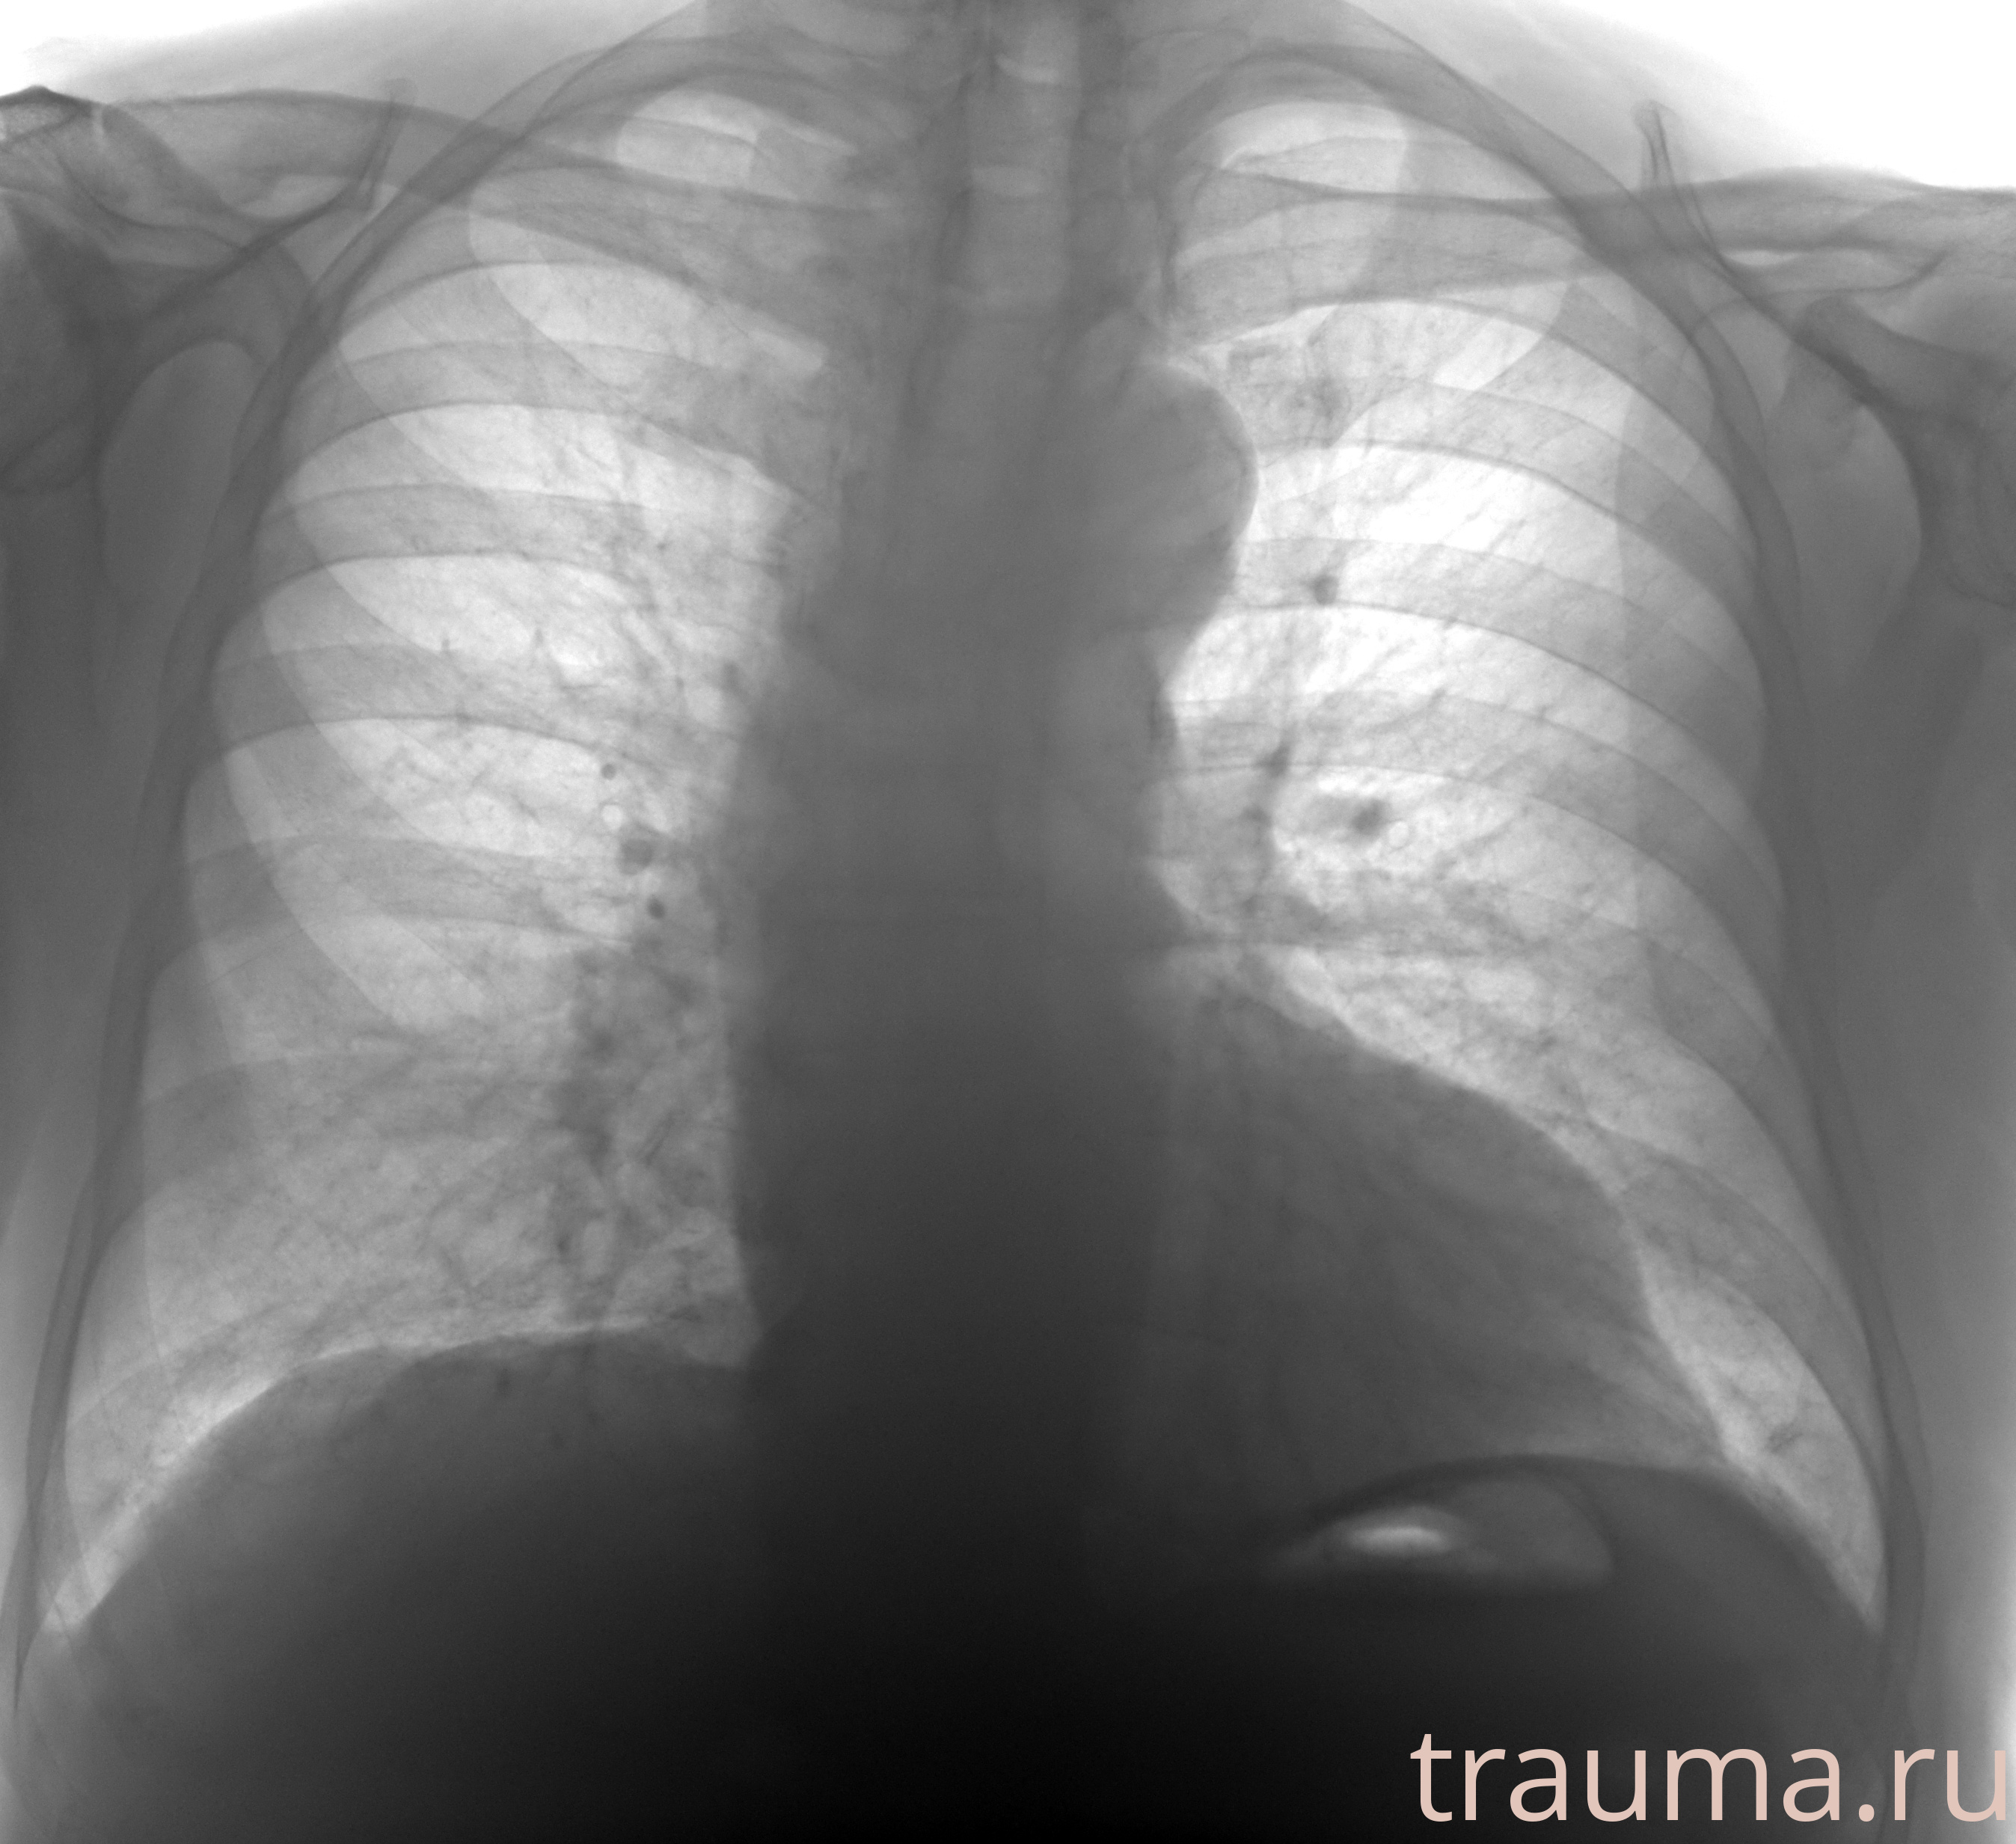

Рентген на дому: по вашему адресу приезжает врач-рентгенолог, травматолог-ортопед с мобильным рентгеновским аппаратом, проводит диагностику травмы или заболевания, делает необходимые рентгенограммы, дает рекомендации по дальнейшему лечению. Получить качественные снимки в домашних условиях возможно благодаря уникальной методике, разработанной МосРентген Центром для института  Склифосовского

Яркость: 1   Контраст: 1   Инвертировать: 0 Увеличение: 1

Перетаскивайте мышь вверх/вниз для контраста, влево/право для яркости. Прокрутка колесом изменяет масштаб. Нажмите Сбросить для возврата к исходному изображению. При увеличении держите мышь в той области, которую хотите рассмотреть.